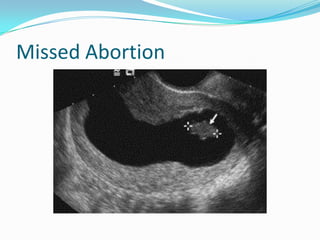

Missed Abortion